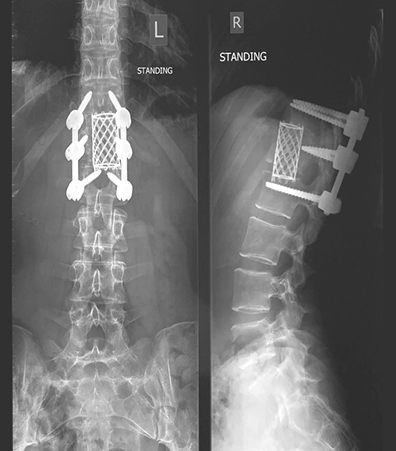

Позвонки поочередно издали хрустящий звук. Это «хрусть-хрусть-хрусть-хрусть-хрусть-хрусть-хрусть» прошло весь путь вверх до моего второго грудного позвонка, который не выдержал давления и разлетелся на четырнадцать осколков.

Следующие две недели я пролежала пластом на больничной койке в ожидании операции на позвоночнике. Будучи не в силах заснуть, продолжала мысленно рисовать картину того, что мне предстояло перенести. В это было невозможно поверить: хирург собирался вскрыть мое туловище, сначала сбоку, на уровне талии, а затем сзади, на уровне разрушенного позвонка. Он планировал извлечь костные фрагменты вместе с двумя соседними дисками, а потом соединить три позвонка вместе и скрепить позвоночник шестью металлическими стержнями длиной 7,5 сантиметра. Отверстия для них нужно было просверлить электродрелью.

Конечный результат. (Нет, рамка металлоискателя в аэропорту не звенит, и да, эти стержни останутся во мне навсегда.)